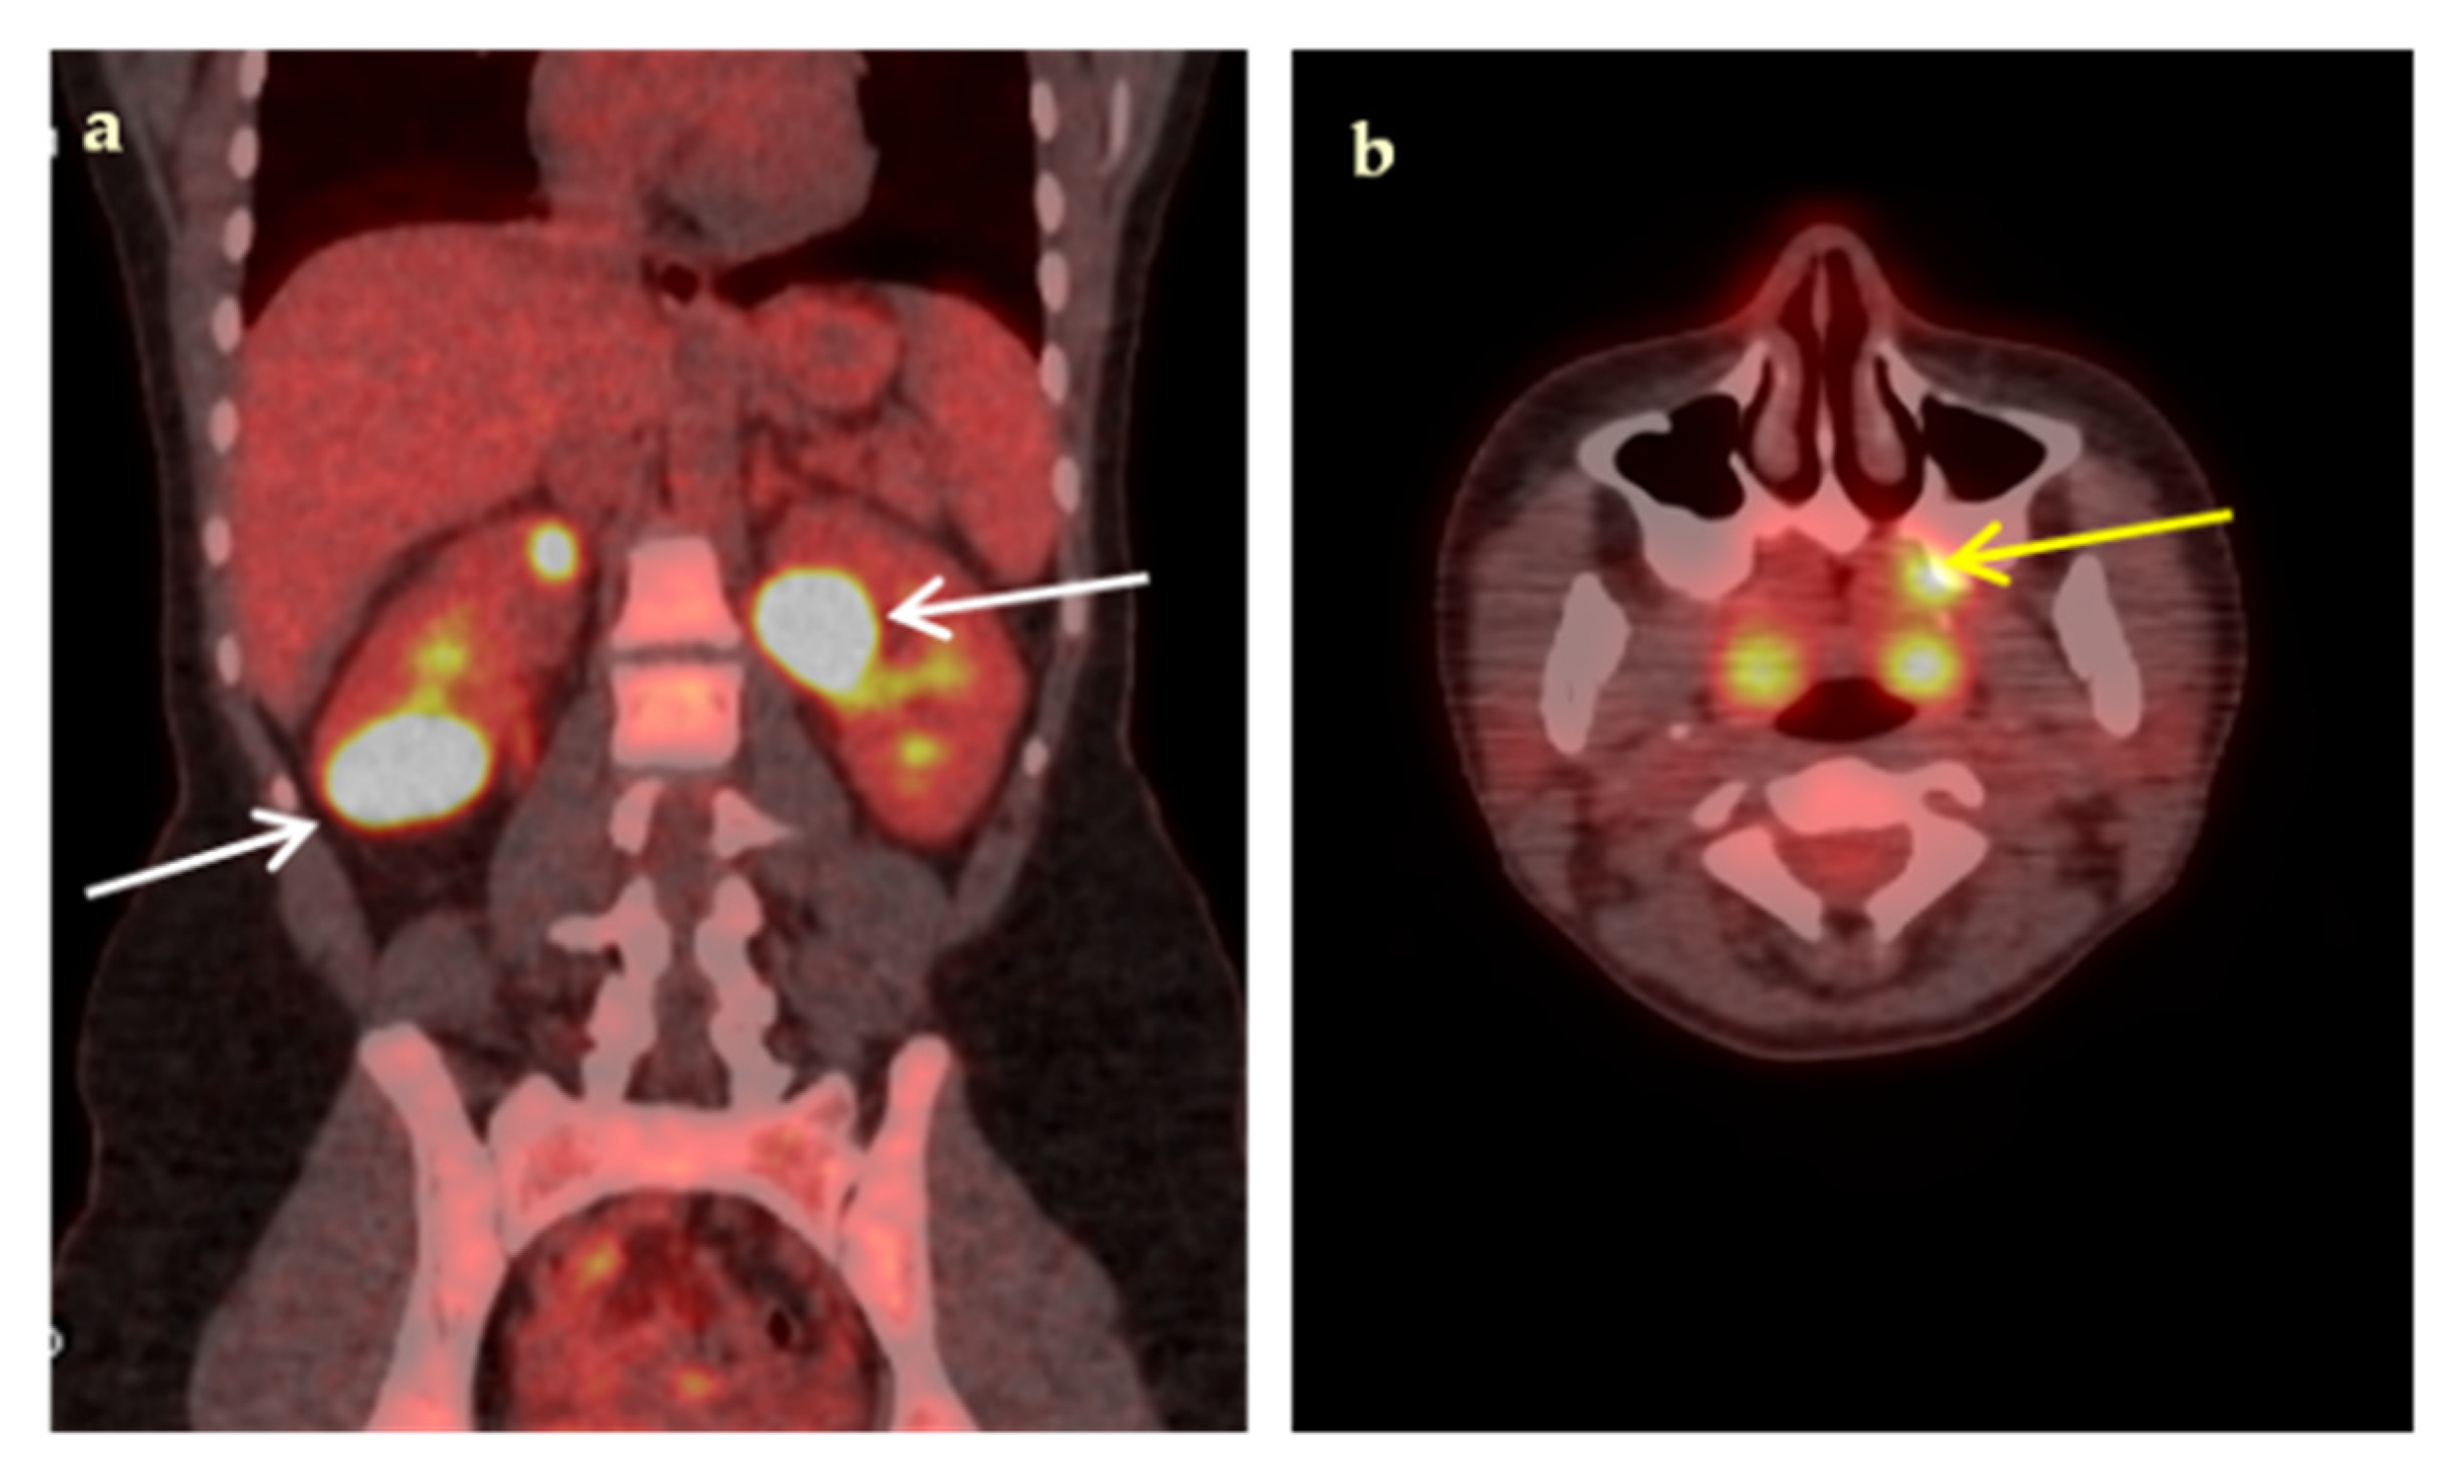

| Infections | 20 (40%) |

| Abdominal abscesses | 4 |

| Infectious cyst in polycystic renal disease | 3 |

| Pneumonia/inflammation of bronchiectasis cysts | 3 |

| Vascular graft infection | 3 |

| Tuberculous spondylitis | 1 |

| Bacterial spondylodiscitis | 1 |

| Pulmonary tuberculosis | 1 |

| CIED-associated infection | 1 |

| Infectious lymphadenopathy | 1 |

| Cryptococcosis | 1 |

| Leishmaniasis | 1 |

| Malignancy | 8 (16%) |

| Non-Hodgkin’s lymphoma | 5 |

| Hodgkin’s disease | 1 |

| Lung cancer | 1 |

| Relapse of urinary tract carcinoma | 1 |

| Non-infectious Inflammatory diseases (NIID) | 11 (22%) |

| Large vessel vasculitis/Takayasu’s arteritis | 3 |

| Adult-onset Still’s disease | 2 |

| Sarcoidosis | 1 |

| Polymyalgia rheumatica | 1 |

| Inflammatory bowel disease | 1 |

| Familial Mediterranean fever | 1 |

| Neo-esophagus inflammation from gastroesophageal reflux | 1 |

| Subacute thyroiditis | 1 |